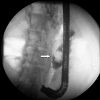

Image 2. Fluoroscopic image during endoscopic retrograde cholangiography revealing Type I choledochal cyst containing stone (arrow)